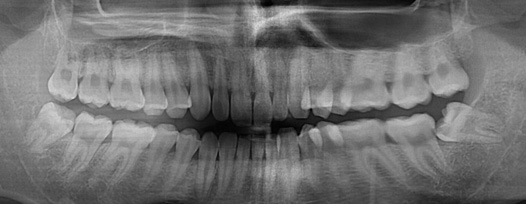

청담네오플란트에서는 전문의료진들이 첨단 의료장비와 객관적인 시각자료를 통해 충치의 단계를 정확하게 진단하여 환자분들께 자세한 설명을 드린 후 단계 별로 꼭 필요한 치료만을 진행하고 있습니다.

청담네오플란트는 3D CT 촬영 후 전문의료진들의 정확한 분석으로 안전하게 사랑니를 발치합니다.

사랑니의 크기와 방향, 깊이, 뿌리 상태 등과 구강검진을 실시합니다.